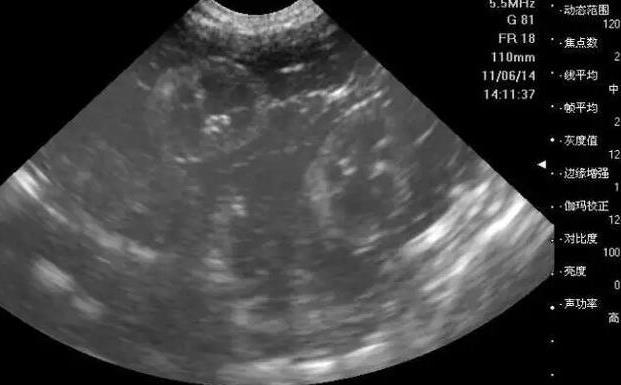

廈門安寶醫(yī)院試管流程中接下來(lái)要做的就是把卵子給取出來(lái),然后完成體外受精,醫(yī)生會(huì)在B超的引導(dǎo)下用特殊的取卵針經(jīng)過陰道穿刺成熟的卵泡,然后把卵子給取出來(lái),把卵子取出來(lái)的同時(shí)是在靜脈麻醉下進(jìn)行的,因?yàn)榇蠖鄶?shù)的女性可能并不會(huì)感染穿刺過程中所導(dǎo)致的痛苦,而體外受精也是非常重要的,精液,經(jīng)過特殊的洗滌之后,完全可以把精子和卵子放在特殊的培養(yǎng)基當(dāng)中,這就是所謂的常規(guī)受精方式。